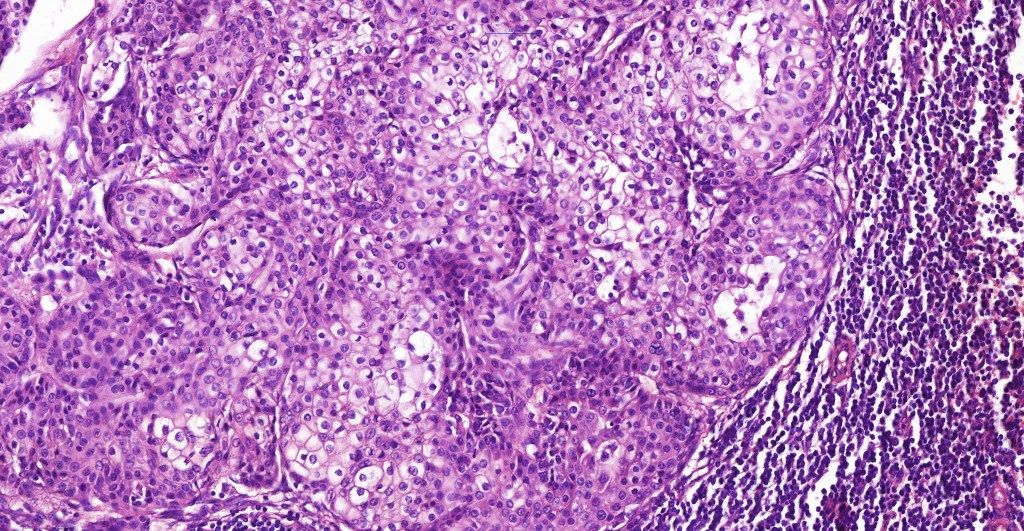

Histological features

•Solid or cystic sharply defined nodule in dermis sometimes extending into subcutaneous fat

•Generally composed of an admixture of small eosinophilic cells & glycogen-rich larger clear cells

•Round to oval vesicular nuclei with small nucleoli or hyperchromatic nuclei

•Ductal and glandular differentiation

•Goblet cells are not uncommon

•Hyaline collagenous stroma